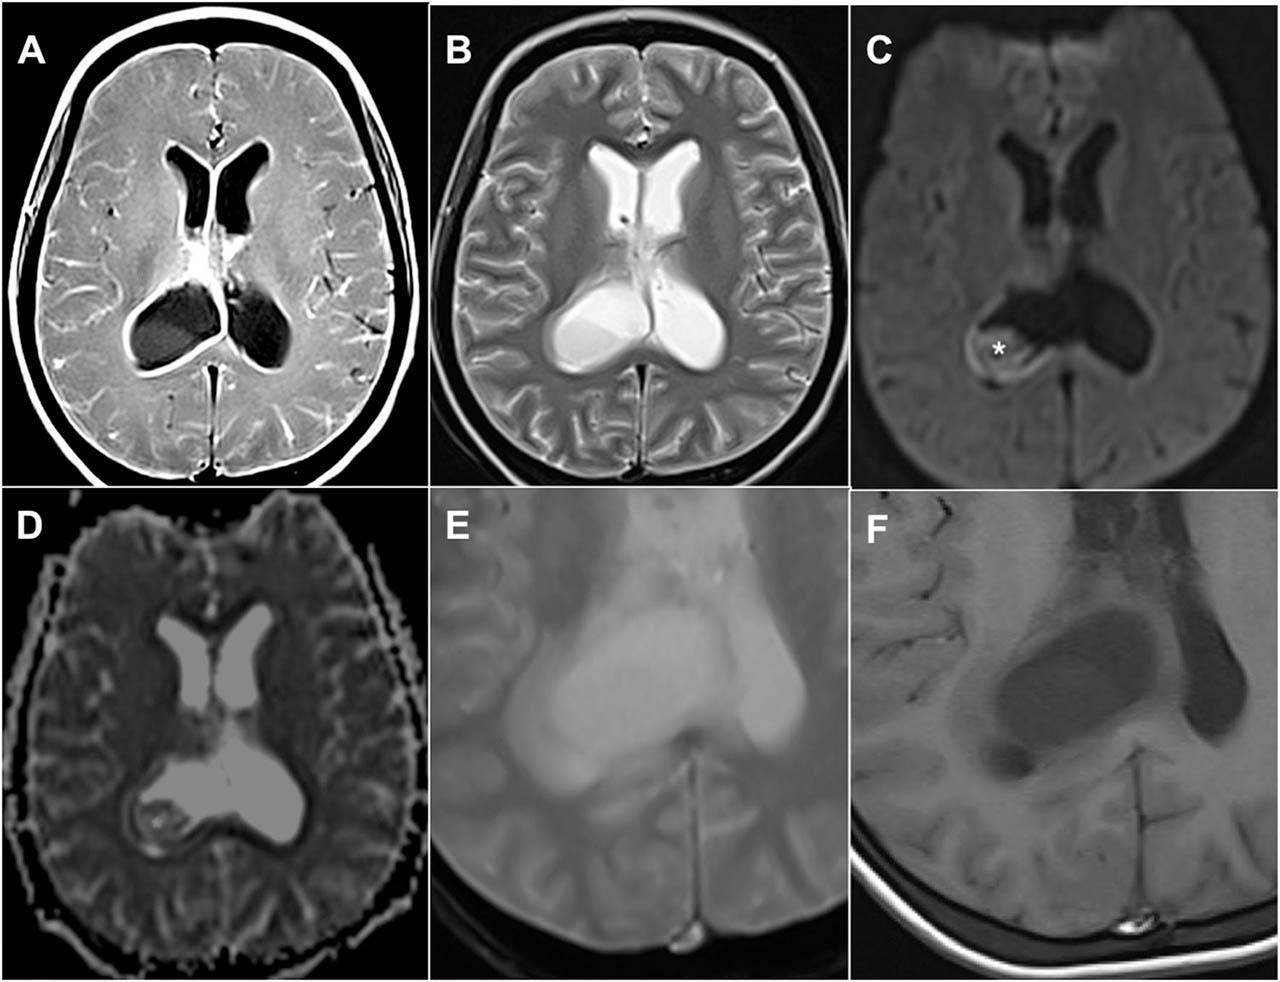

Axial images of (A) plain and (B) contrast computed tomography of the brain show a cystic lesion within the right lateral ventricles with sediments and septations within. There is also a minimal rim enhancement of the wall (arrow) and dilatation of both lateral ventricles consistent with hydrocephalus.

Figure 2

Axial magnetic resonance imaging of the brain shows hydrocephalus and the tuberculous abscess, which is a collection within the posterior horn of the right lateral ventricle. The (A) T1W post contrast image shows rim enhancement of the wall of the lesion, and the ependymal lining of both lateral ventricles and along the cortical gyri. (B) A T2W image shows hyperintense signal of the core of the lesion with an incomplete hypointense rim of the wall. (C) Diffusion-weighted image and the corresponding (D) apparent diffusion coefficient map demonstrate mild diffusion restriction (*) at the inferior aspect of the lesion. Close-up of axial images on (E) T2*-weighted gradient-echo and (F) T1W sequences. No evidence of a hypointense rim is seen in the gradient-echo image. T1W, T1-weighted; T2W, T2-weighted.